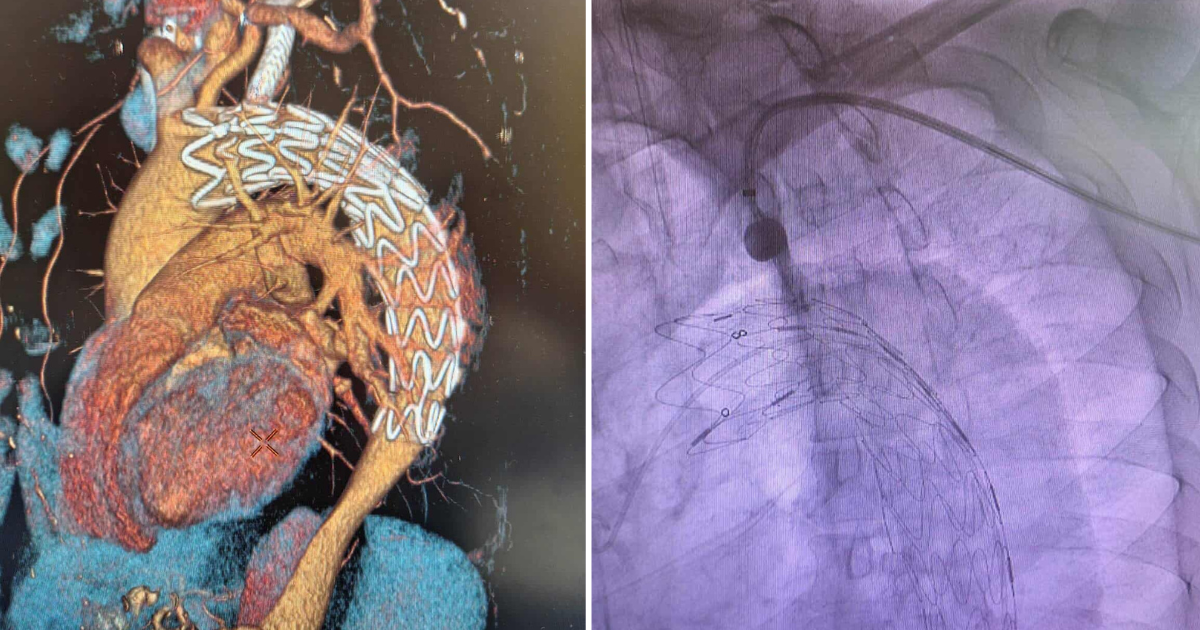

Во Клиничката болница „Аџибадем Систина“ првпат во Македонија беше изведена комплексна ендоваскуларна процедура на торакалната аорта – ТЕВАР со т.н. in situ фенестрација за левата потклучна артерија кај пациент со постдисекциска аневризма на десцендентната торакална аорта.

„Станува збор за интервенција при која се постави стент на делот од аортата кој беше заболен, при што интенционо со стентот се покри излезот во аортата за левата потклучна артерија за да се обезбеди стабилност на стентот во здрава аорта. Потоа преку артеријата на левата рака со посебна направа се направи отвор на стентот на ниво на аорта низ кој се постави нов стент кој обезбедува проток низ артеријата за левата рака. Со ова пациентот избегнува дополнителна операција на крвните садови на вратот (бајпас), избегнува двојна анестезија за краток временски интервал, крвозагуба, а и значајно се скратува рехабилитацијата. Интервенцијата помина во најдобар ред, а пациентот одлично ја поднесе и по два дена ја напушти болницата на домашно лекување“, објаснува д-р Лазовски.